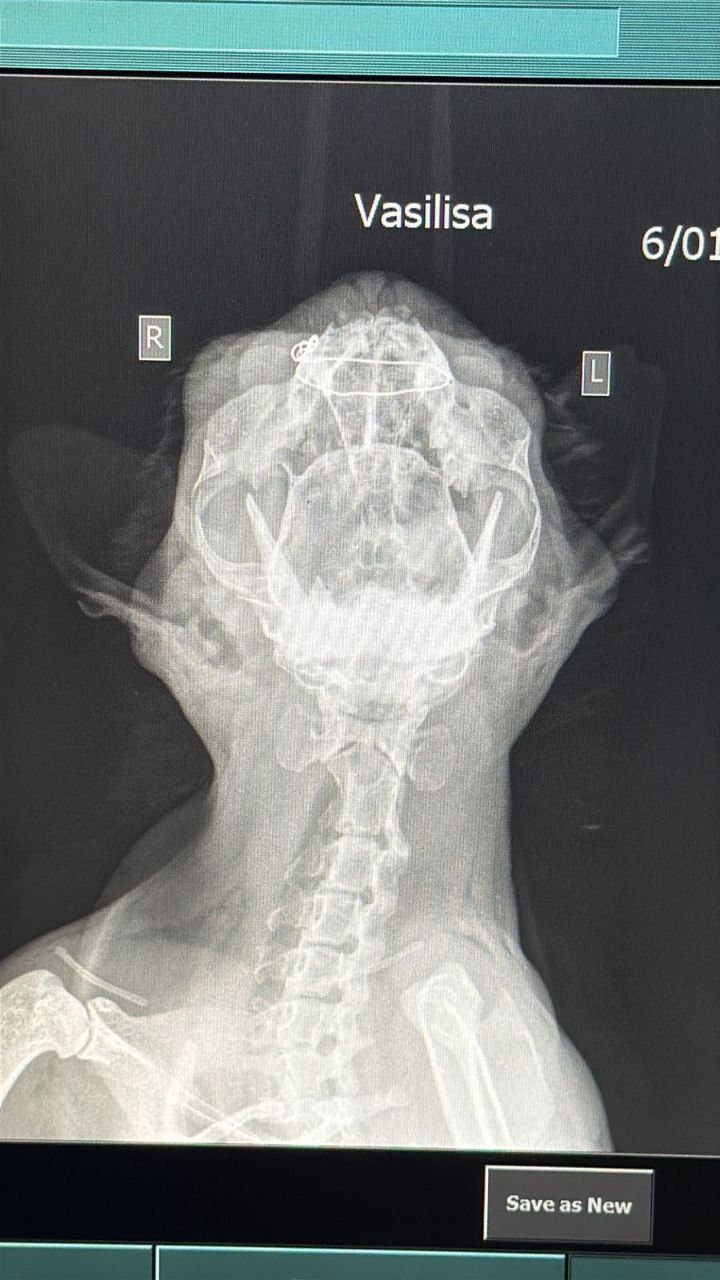

Рентген делали; если я правильно поняла во время операции сделали конструкцию из проволоки для верхней челюсти (сломана) и зашили губу, кошку ждёт восстановление до месяца.. Но в клинике ток несколько дней, дальше надо будет домой забирать

@MaraJadeSКошка Василиса чувствует себя средне, но прогноз хороший - вчера сделали рентгены и операцию, сделали конструкцию из проволоки на сломанную верхнюю челюсть и два шва на губу. Кошечке ставят все необходимые лекарства и кормят внутривенно, её ждёт долгое восстановление с челюстью, но она такая ласковая даже после ДТП и операций, что просто сердце разрывается 💔 Я очень надеюсь что у меня получится оставить её на восстановление у себя, несмотря на аллергию